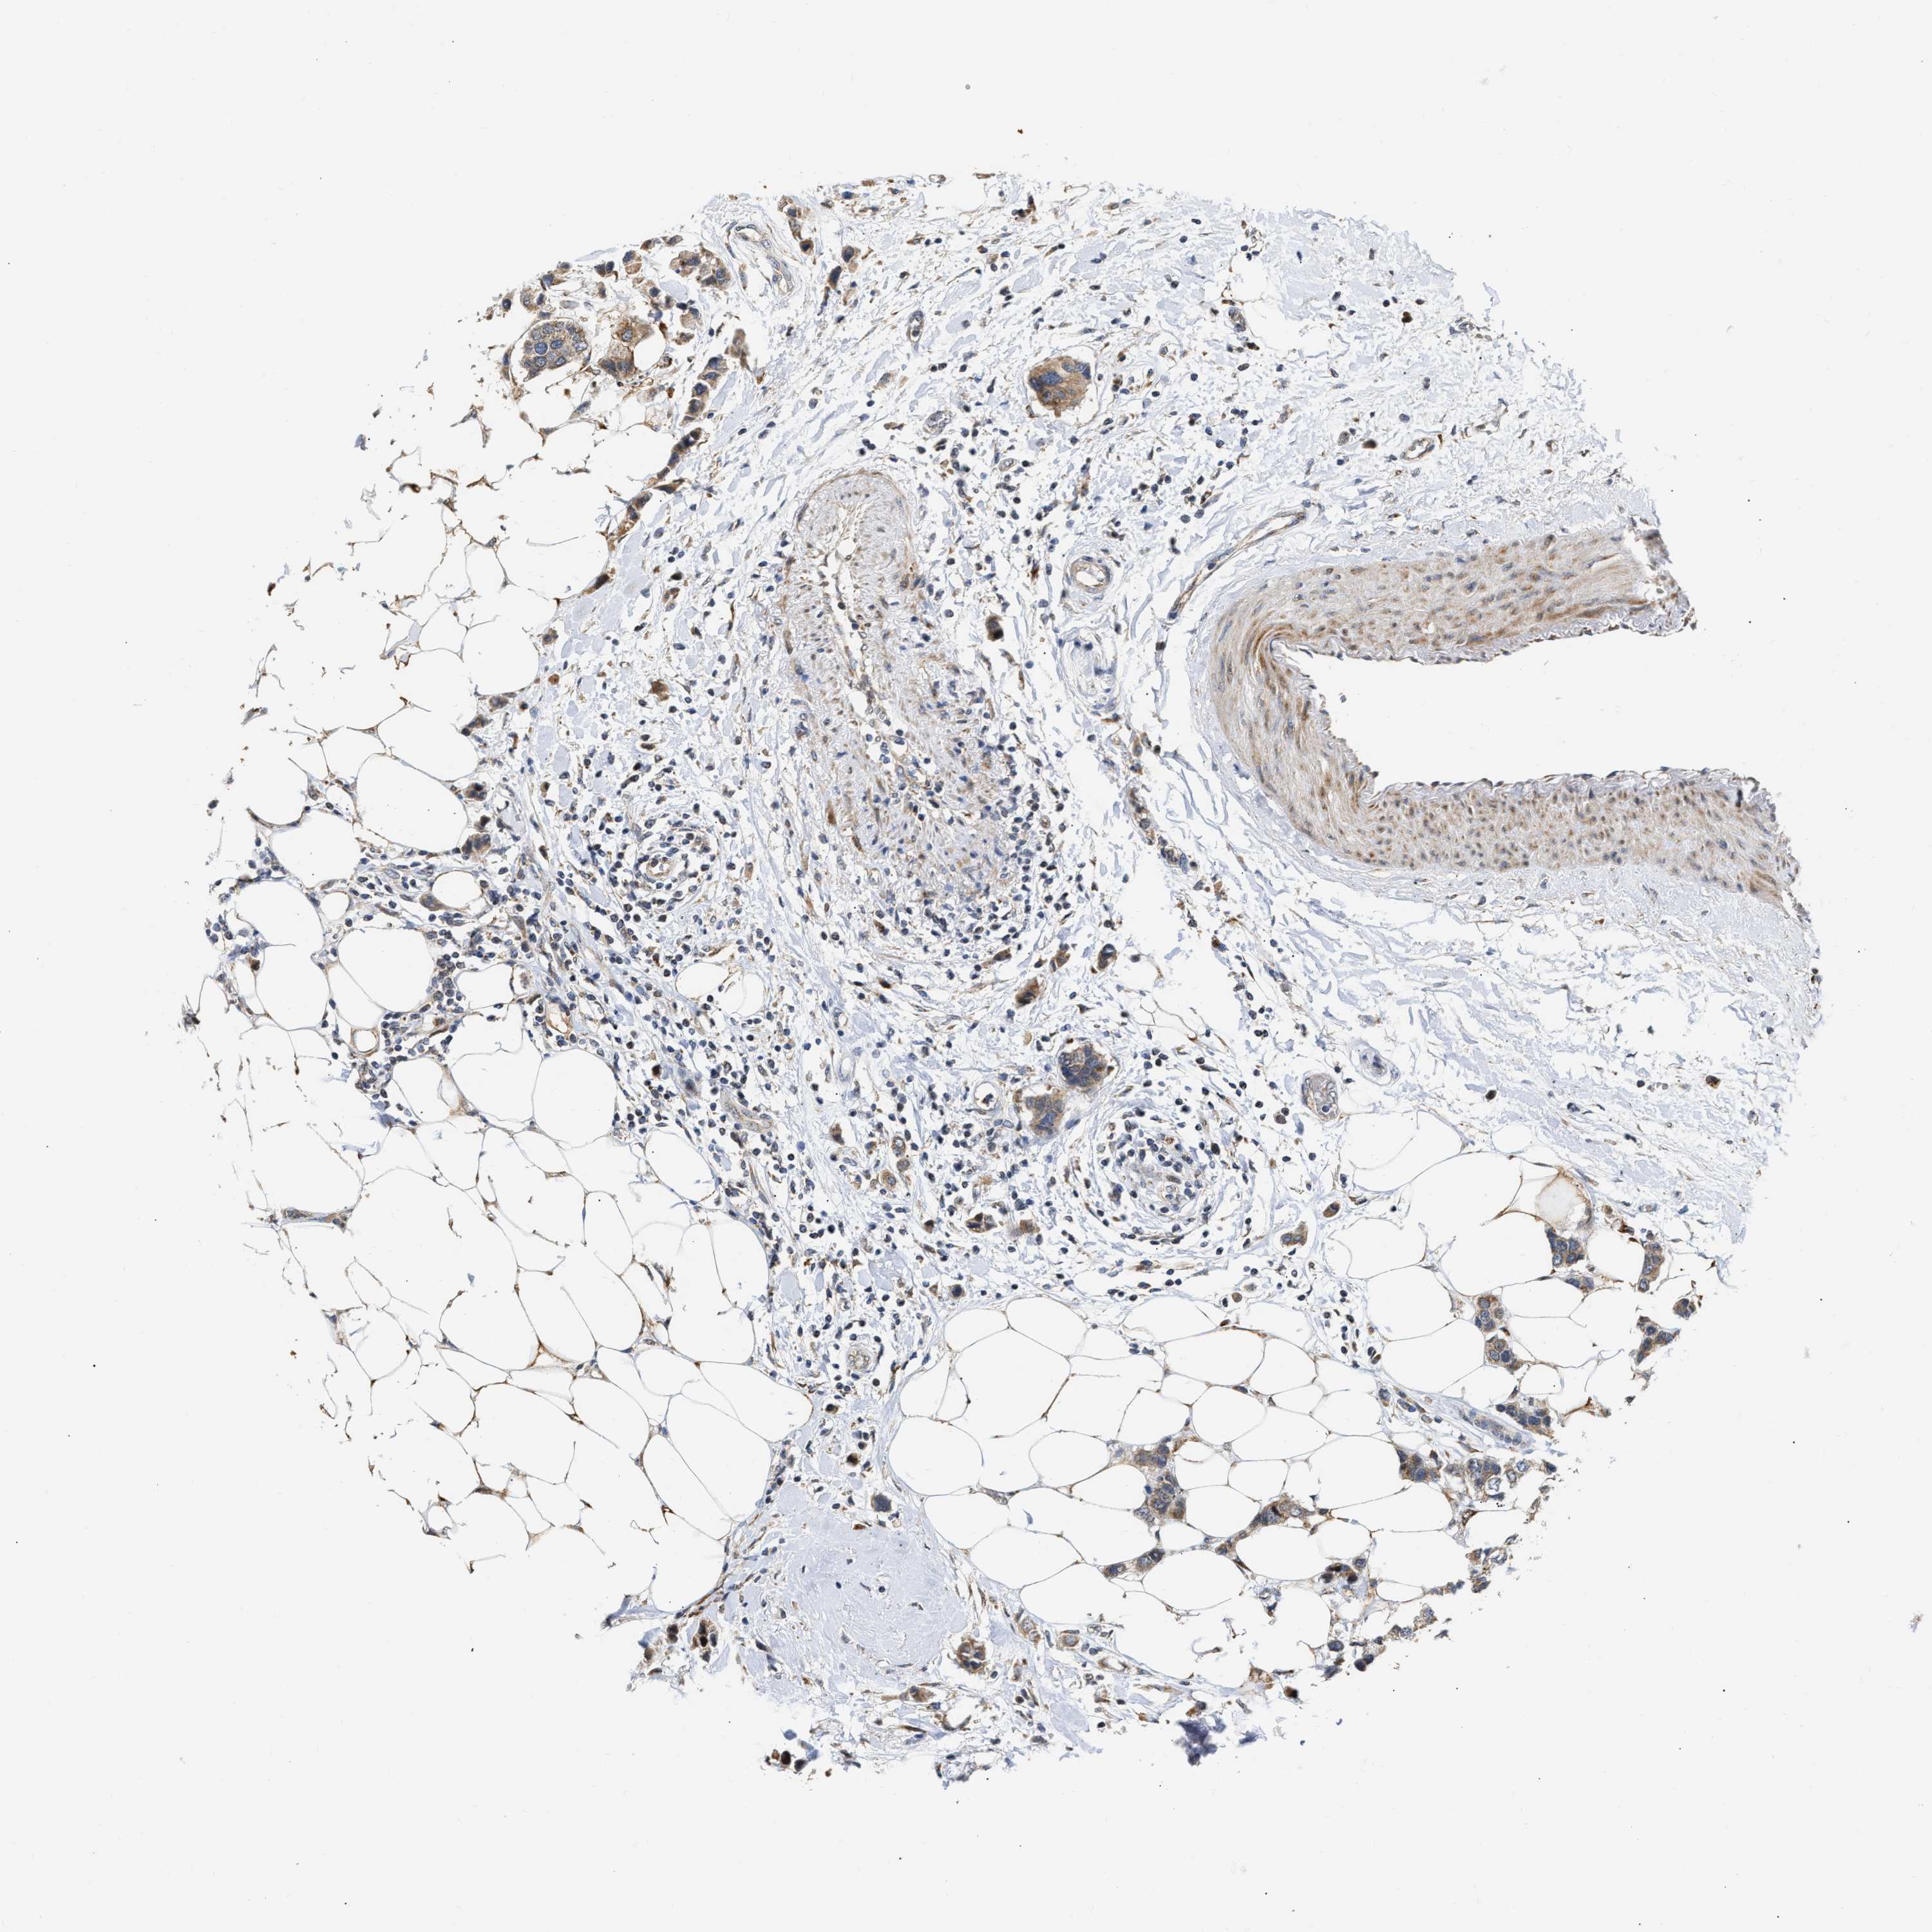

BRCA TCGA BRCA VALIDATION PROTEIN EXPRESSION